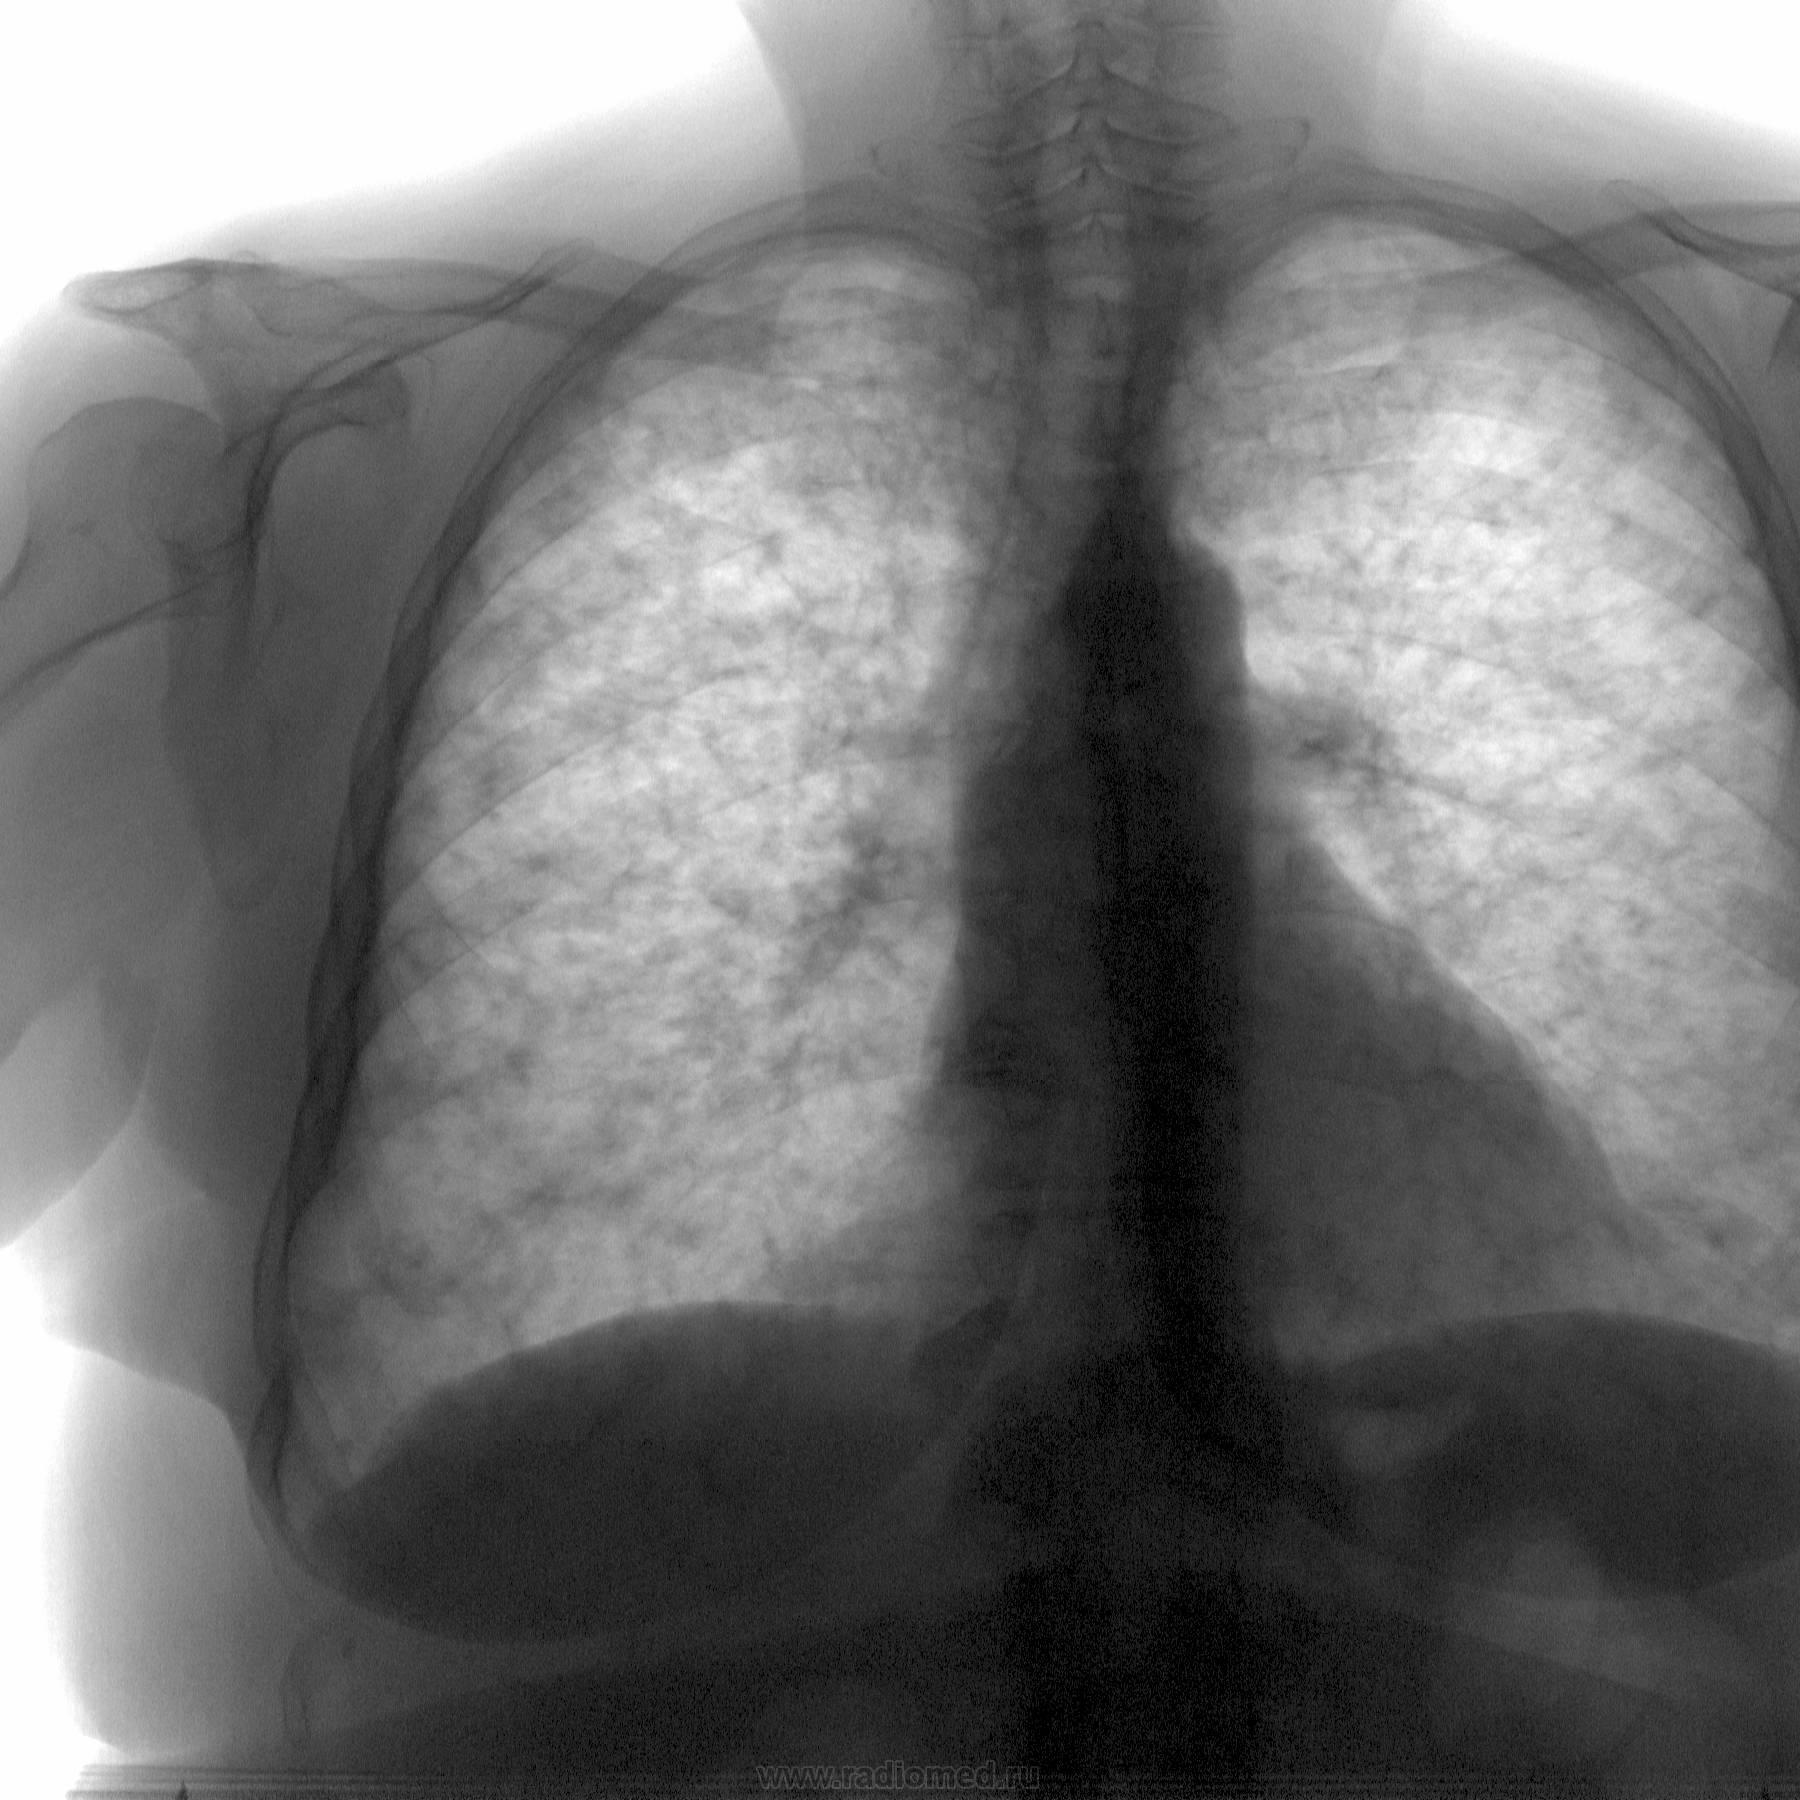

Синдром внутрилёгочной диссеминации.Нужен ФЛО-архив (давность изменений ?) Необходимо дифференцировать:

1.Диссеминированный туберкулёз

2 Саркоидоз лёгочная форма.

3. Интерстициальная пневмония

4.Канцероматоз лёгких.

Названо "снежит".

А вот и архив за февраль прошлого года, который просил Александр.

На архивном снимке справа медио-базально снижение прозрачности, которого видно поменее на "свеженьком" снимке...

Впрочем на "свеженьком" и корни слабовать видны из-за того, что "снежит"...

Такие картиночки, особенно при рентгеноскопии, да в темном кабинете, как свидетельствовали аксакалы "того времени", могли быть только при милиарном

Хочется исключить из дифряда канцероматоз - прикорневые зоны относительно чистые. Я больше склоняюсь к туберкулезу

Наверное tbc- при равномерное диссеминации все- таки более плотно они расположены на верхушках.

Ещё раз посмотрел, снимки- такое чувство, что в очагах диссеминации присутствуют вкрапаления извести( зоны казеоза), что характерно для туберкулёзного поражения . Вывод: больше данных туберкулёзное поражение, по типу хронического диссеминированного туберкулёза ( с учётом ФЛО-архива давность заболевания до 1 года)- но, это конечно ИМХО.

Если отбросить скиалогические наложения, то, по всей видимости, на томограммах диссеминация будет довольно мономорфная.

Что то уж густо снежит, не похоже на ТБ. Или вправду хронический диссеминированный, которого уже так часто не встретишь, не с чем и не с кем сравнить.